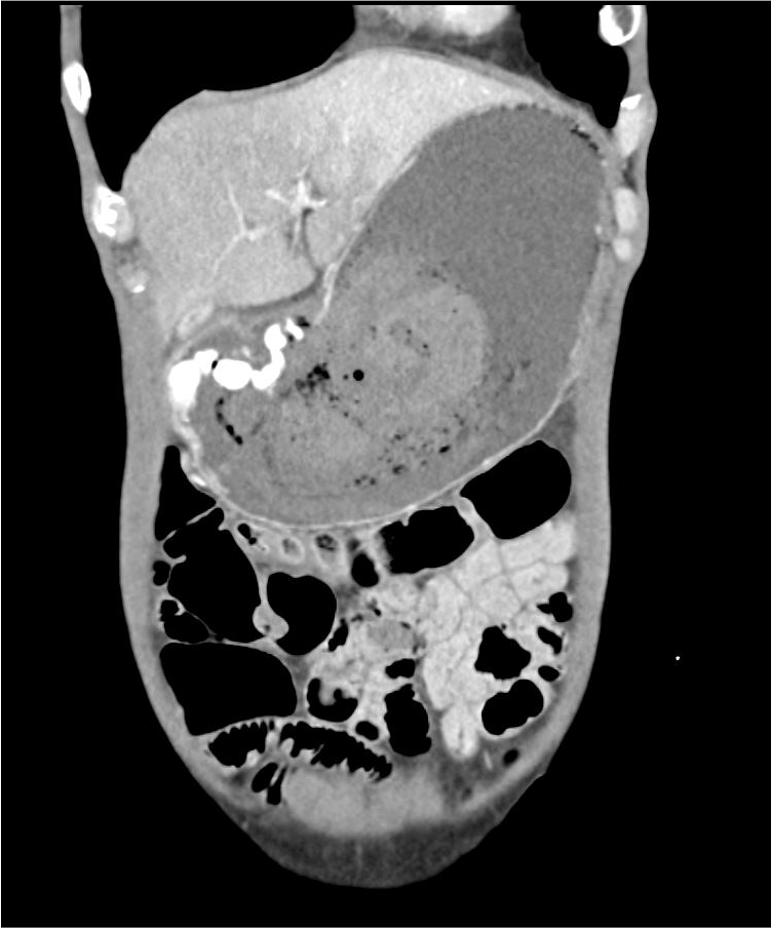

消化器内科 第28号(Vol.4 No.3,2022)特集:体外式超音波による。消化器内科 第28号(Vol.4 No.3,2022)特集:体外式超音波による。肝臓疾患(一般・消化器外科・胃腸科) | 医療法人清仁会 水無瀬病院。消化管間質腫瘍 (GIST) | KOMPAS – 慶應義塾大学病院 医療。「消化管疾患」井村 裕夫 / 日野原 重明 / 千葉 勉定価: ¥ 9800#井村裕夫 #井村_裕夫 #日野原重明 #日野原_重明 #千葉勉 #千葉_勉 #本 #自然/医療・薬学・健康

• 消化器内科 第28号(Vol.4 No.3,2022)特集:体外式超音波による

• 肝臓疾患(一般・消化器外科・胃腸科) | 医療法人清仁会 水無瀬病院

• 消化管間質腫瘍 (GIST) | KOMPAS – 慶應義塾大学病院 医療